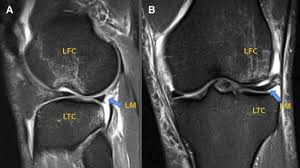

Lateral aspect of medial femoral condyle most common location. The motions of the condyles include rocking, gliding and rotating. In the knee, chondromalacia is usually related to injury, overuse of the knee, and poorly aligned muscles and bones around the knee joint. Methods sixteen knees with a small medial femoral. When ocd affects the knee, the most common location is within the lateral aspect of the medial femoral condyle. Medial condyle of femur from wikipedia, the free encyclopedia the medial condyle is one of the two projections on the lower extremity of femur, the other being the lateral condyle. The femoral condyle allograft has been used for resurfacing cartilage defects with mature hyaline cartilage for several decades, with very high success rates. The medial femoral condyle is supplied by a plexus of vessels from the descending genicular artery and the medial superior genicular artery.

The radiographs demonstrated abnormal contour of the medial femoral condyle, consistent with an osteochondral defect, and a fabella posterior to the knee. Methods sixteen knees with a small medial femoral. It acts to support a significant amount of the patient's body weight. An imbalance of the muscles around the knee (some muscles are weaker than others.) overuse (repeated bending or twisting) of the knee joint, especially during sports. If there is a fracture (break) in part of the condyle, this is known as a fracture of the femoral condyle. The medial femoral condyle is supplied by a plexus of vessels from the descending genicular artery and the medial superior genicular artery. Damage may also be the result of a direct blow to the knee. Palpable to either side of the knee joint when it is bent, they are known specifically as the medial and lateral femoral condyles.